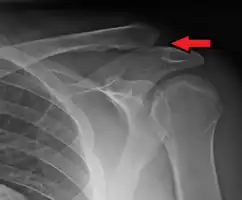

| An Xray showing a separated shoulder. Notice the separation between the end of the collarbone and the scapula. | |

A separated shoulder, also known as acromioclavicular joint injury, is a common injury to the acromioclavicular joint.[2] The AC joint is located at the outer end of the clavicle where it attaches to the acromion of the scapula.[2] Symptoms include pain which may make it difficult to move the shoulder and often a deformity.[2][1]

It is most commonly due to a fall onto the front and upper part of the shoulder when the arm is by the side.[2] They are classified as type I, II, III, IV, V, or VI with the higher the number the more severe the injury.[2] Diagnosis is typically based on physical examination and X-rays.[2] In type I and II injuries there is minimal deformity while in a type III injury the deformity resolves upon lifting the arm upwards.[2] In type IV, V, and VI the deformity does not resolve with lifting the arm.[2]

X-ray indicates a separated shoulder when the acromioclavicular joint space is widened (it is normally 5 to 8 mm),[11]it can be classified into 6 types.